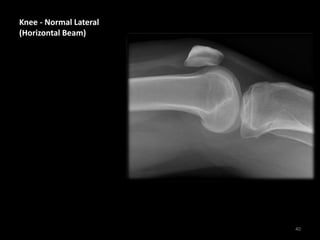

Knee - Normal Lateral

(Horizontal Beam)

• The Horizontal Beam

Lateral view is useful

for assessing soft

tissues as well as bones

• The quadriceps and

patellar tendons are

visible

• Note the normal

suprapatellar pouch

between fat pads

above the patella

(asterisks) - widening

of these fat pads or

increased density in

this area can indicate a

knee joint effusion

41